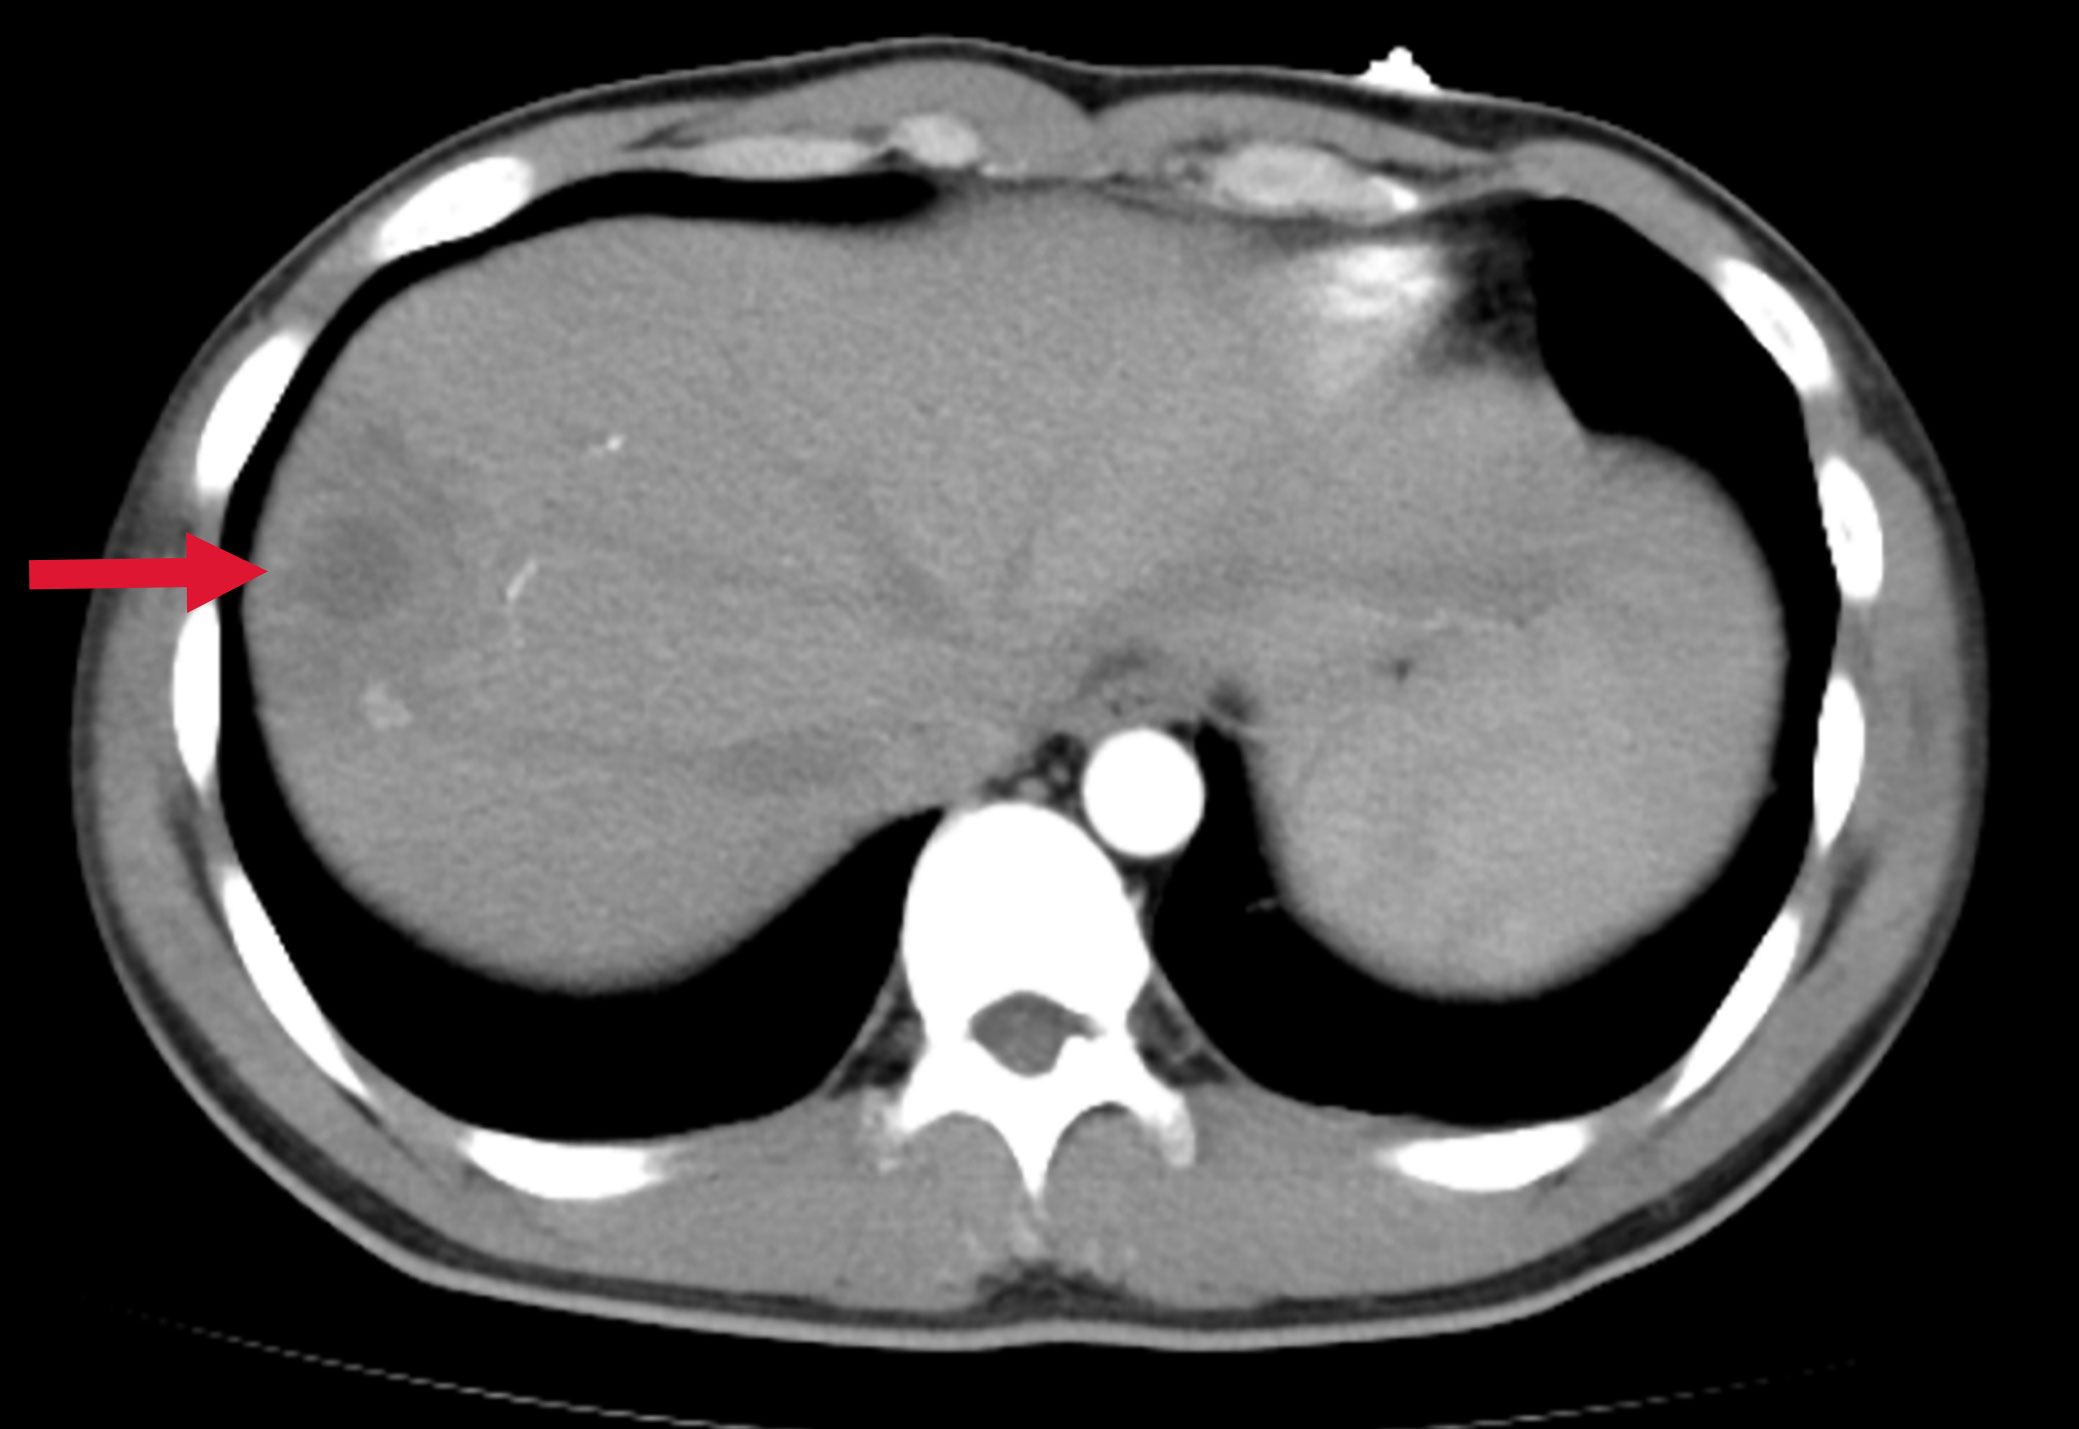

A previously healthy 25-year-old male developed high fever (maximum 40°C) without an identifiable cause while traveling in Jiangxi, China. The fever was accompanied by mild cough and sputum production. Despite self-medicating with over-the-counter cold medication, his symptoms persisted. Five days later, he experienced sudden onset of blurred vision, redness, and painful swelling in his left eye. After nearly a week of persistent symptoms without improvement, he underwent a chest CT scan, which revealed a pulmonary mass, prompting further evaluation. Upon hospital admission on August 2, 2024, CT imaging demonstrated multiple pulmonary nodules with partial cavitation, suggesting a possible infectious etiology (Figure 1). Orbital CT revealed an intraocular mass in the left eye, with irregular margins of the left globe and heterogeneous attenuation in the peribulbar and orbital apex tissues (Figure 2). Additionally, a low-density hepatic lesion was identified (Figure 3), raising suspicion of a liver abscess, and a low-density nodule was detected in the right thyroid lobe. Laboratory tests revealed leukocytosis and significantly elevated inflammatory markers, leading to the initiation of empiric antibiotic therapy with ceftriaxone sodium. Two sets of peripheral blood cultures collected on August 4, 2024 (left and right upper limbs) were negative; blood cultures were not repeated. Due to patient non-cooperation, a complete ophthalmologic evaluation of the left eye was not feasible. Hemodynamics remained stable without vasopressors (SBP 110–130 mmHg/DBP 70–85 mmHg); lactate was 1.2 mmol/L, urine output was ≥1 mL/kg/h, and mental status was normal, indicating no clinical evidence of septic shock. On August 5, 2024, bronchoalveolar lavage fluid (BALF) culture grew K. pneumoniae without detected antimicrobial resistance. Metagenomic next-generation sequencing (mNGS) of bronchoalveolar lavage (BAL) fluid further confirmed the presence of K. pneumoniae. Given the severity of the infection, the antimicrobial regimen was escalated to meropenem. Despite intensive antimicrobial therapy, the infection progressed rapidly, affecting multiple organ systems. The patient was diagnosed with invasive K. pneumoniae syndrome, characterized by pulmonary abscess, liver abscess, thyroid nodule, and endogenous endophthalmitis with retinal detachment. Given the disseminated nature of the infection, the antimicrobial regimen was further adjusted to meropenem plus levofloxacin. Although systemic infection was gradually controlled, the left eye infection continued to deteriorate. The patient developed worsening ocular pain and progressive vision loss. Ophthalmologic evaluation revealed scleral ulcer perforation with extensive orbital tissue necrosis, resulting in irreversible ocular damage. Due to the severity of the infection, on August 21, 2024, the patient underwent left ocular enucleation. Postoperative ocular tissue cultures confirmed K. pneumoniae infection. Following surgery, the antimicrobial regimen was adjusted from meropenem plus levofloxacin to cefoperazone-sulbactam. By the time of discharge, follow-up imaging demonstrated a reduction in pulmonary and hepatic abscess size, with adequate infection control. Figure 4 illustrates the detailed course of disease progression.

Figure 3. Abdominal CT showing a low-density lesion with ill-defined borders in the right lobe of the liver, suggestive of a hepatic abscess. The red arrow indicates the abscess site.